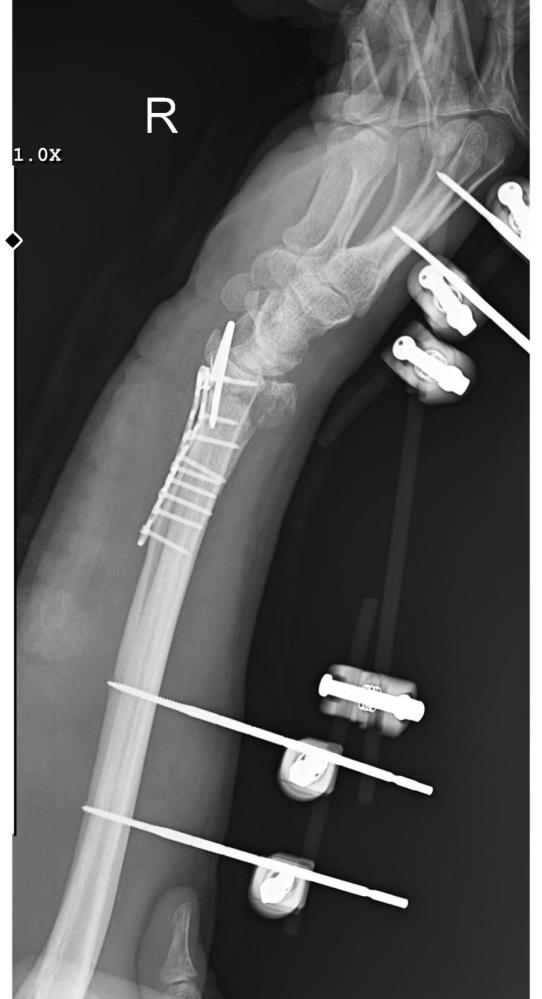

Olay, 29 Aralık günü Mamak’ta meydana geldi. Alınan bilgilere göre, 35 yaşındaki Yasin Arslantaş yaşadığı apartmanın önünde yaklaşık 10 sahipsiz köpek tarafından kovalandı. Kaçmaya çalışırken düşerek el bileği kırılan Arslantaş, ambulansla hastaneye kaldırıldı. Bilek kemiğine 11 adet platin takılan Arslantaş’ın kolunda kalıcı his ve hareket kaybı meydana geldi. Olay nedeniyle maddi ve manevi açıdan zor zamanlar geçirdiği söyleyen Arslantaş, belediye ekiplerinin yaşanan soruna hala çözüm üretmediğini iddia etti.

"Bileğimde 15 dikiş ve 11 platin var"

Yasin Arslantaş, "Sabah apartmandan çıkış yaptığım sırada arkamdan 9 köpeğin geldiğini gördüm. Saldırgan haldelerdi. Bana saldırmak üzerelerdi. Kaçmaya çalışırken ayağım kaydı ve düştüm. Bileğimde 15 dikiş ve 11 platin var. İki ay boyunca kolum bu halde kalacak ve ardından da yine 2 buçuk ay fizik tedavi süreci olacak. Doktorlar his ve hareket kaybımın olacağını söylediler. Bileğimden büyük kemiğin kırılmasından dolayı zorlu bir süreç geçiriyorum. 3 saatlik bir ameliyat geçirdim" dedi.